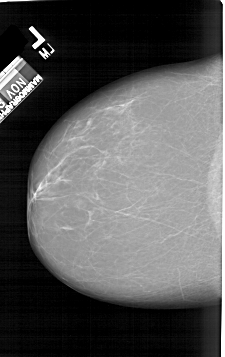

A_1412_1.LEFT_CC

LEFT_CC LINES 6421 PIXELS_PER_LINE 4036 BITS_PER_PIXEL 12 RESOLUTION 43.5 NON_OVERLAY